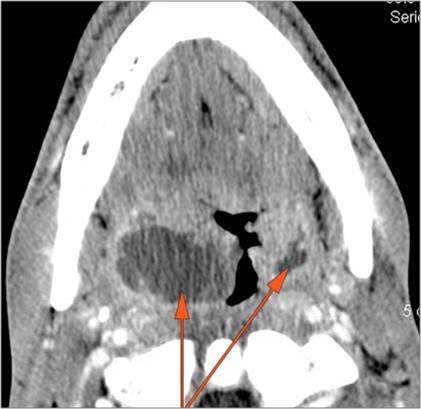

There is abscess at the periphery of the lymphoid tissue of the palatine tonsil within the potential peritonsillar space.

There is abscess within the adjacent deep neck, retropharyngeal and/or prevertebral spaces.

There is significant abnormality of the parotid, submandibular or sublingual glands that would be an alternate explanation for the patient’s symptoms.